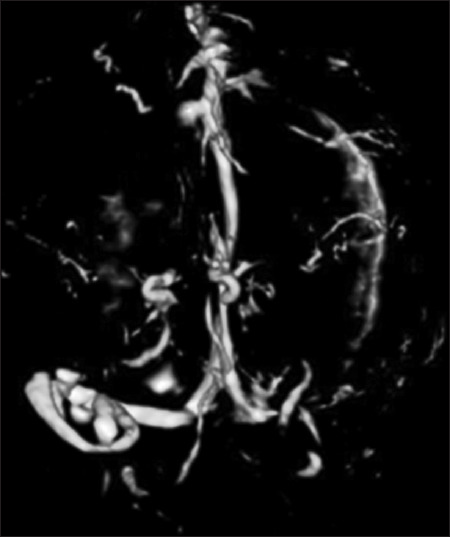

Abstract Image